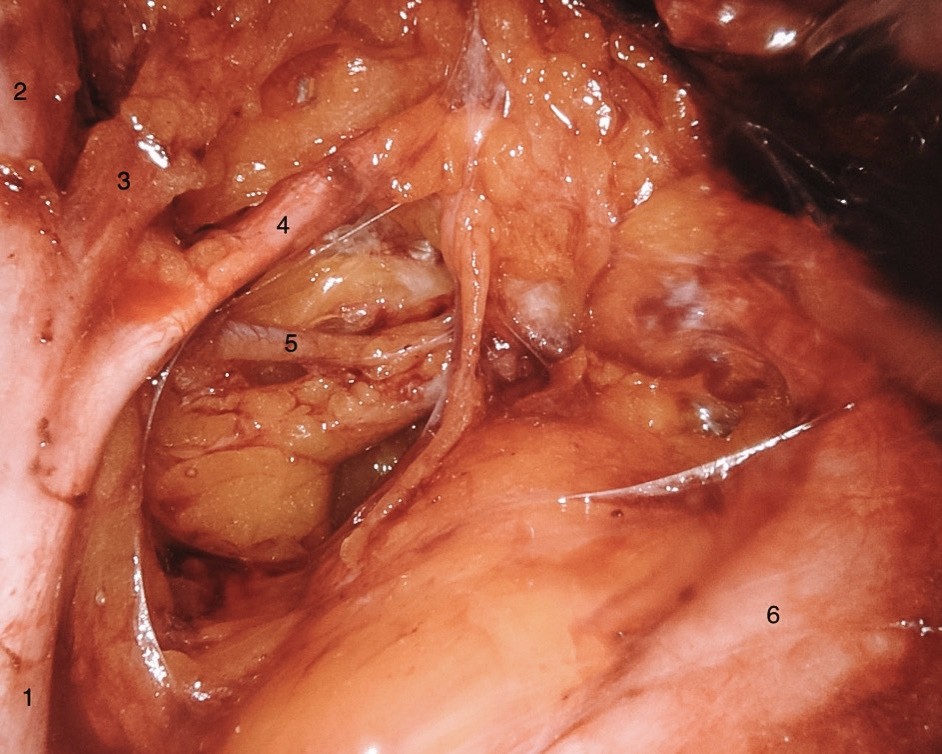

Ο γυναικολόγος-ογκολόγος που εκτελεί τη ριζική υστερεκτομή πρέπει να γνωρίζει άριστα τη χειρουργική ανατομία, και να είναι σε θέση να παρασκευάζει ανατομικές δομές όπως η έσω λαγόνια αρτηρία, η μητριαία αρτηρία, ο ουρητήρας, το υπογαστρικό νεύρο, η άνω φλεβική αρτηρία και η ‚εν τω βάθει φλέβα‘ της μήτρας.

Διεγχειρητική εικόνα του δεξιού πυελικού πλευρικού τοιχώματος που δείχνει 1: την έσω λαγόνια αρτηρία, 2: την ομφαλική αρτηρία, 3: την άνω φλεβική αρτηρία, 4: την μητριαία αρτηρία, 5: την εν τω βάθει φλέβα της μήτρας και 6: τον ουρητήρα